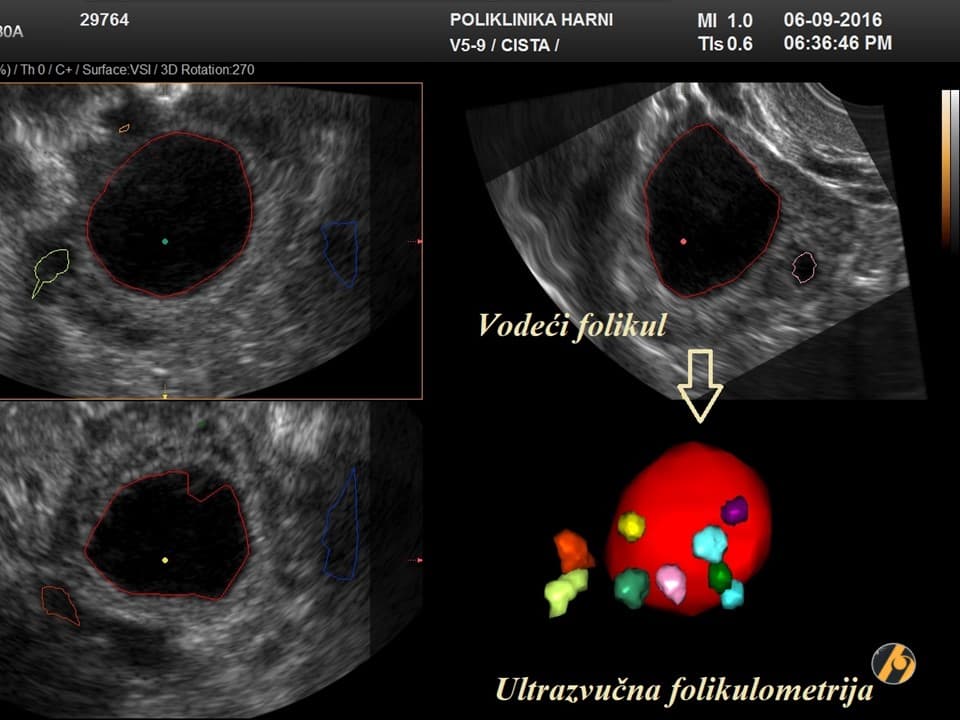

Negdje krajem 2. tjedna od početka menstruacije dolazi do pucanja folikula na jajniku, mjehurića ispunjenog tekućinom, a u kojem se nalazi jajna stanica, što se označuje pojmom ovulacija. Ovulacija je vrijeme najveće plodnosti žene. Jajnu stanicu prihvaćaju jajovodi svojim tankim tereptljikama i tijekom sljedećih 12 do 24 sata transportiraju ju u maternicu. Tijekom ovog putovanja jajne stanice kroz jajovod dolazi do oplodnje. Jajna stanica je sposobna za oplodnju svega nekih 4 sata po ovulaciji, no spermatozoidi mogu živjeti i do tjedan dana u vratu maternice te sačekati na neki način ovulaciju. Spolni odnos u vrijeme ovulacije ne označuje i sigurno nastupanje trudnoće - šansa za rođenjem djeteta iz odnosa u vrijeme ovulacije iznosi oko 35%.